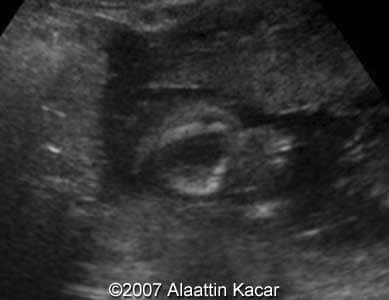

Cleft lip, bilateral Alaattin Kacar, MD Ahmet Celik, MD Merter Keceli,MD. Article Published: Jun 21, 2007 Balikesir, Turkey. These are some images demonstrating bilateral cleft lip of the fetus obtained at 17 weeks of pregnancy. Images 1, 2: Axial images at the level of the upper lip showing bilateral clefts within the upper lip. Images 1, 2: Parasagittal and sagittal images of the fetal head. Parasagittal image shows cleft at the level of the upper lip. Â Â Discussion Board Start a discussion about this article Add to Favorites Favorite